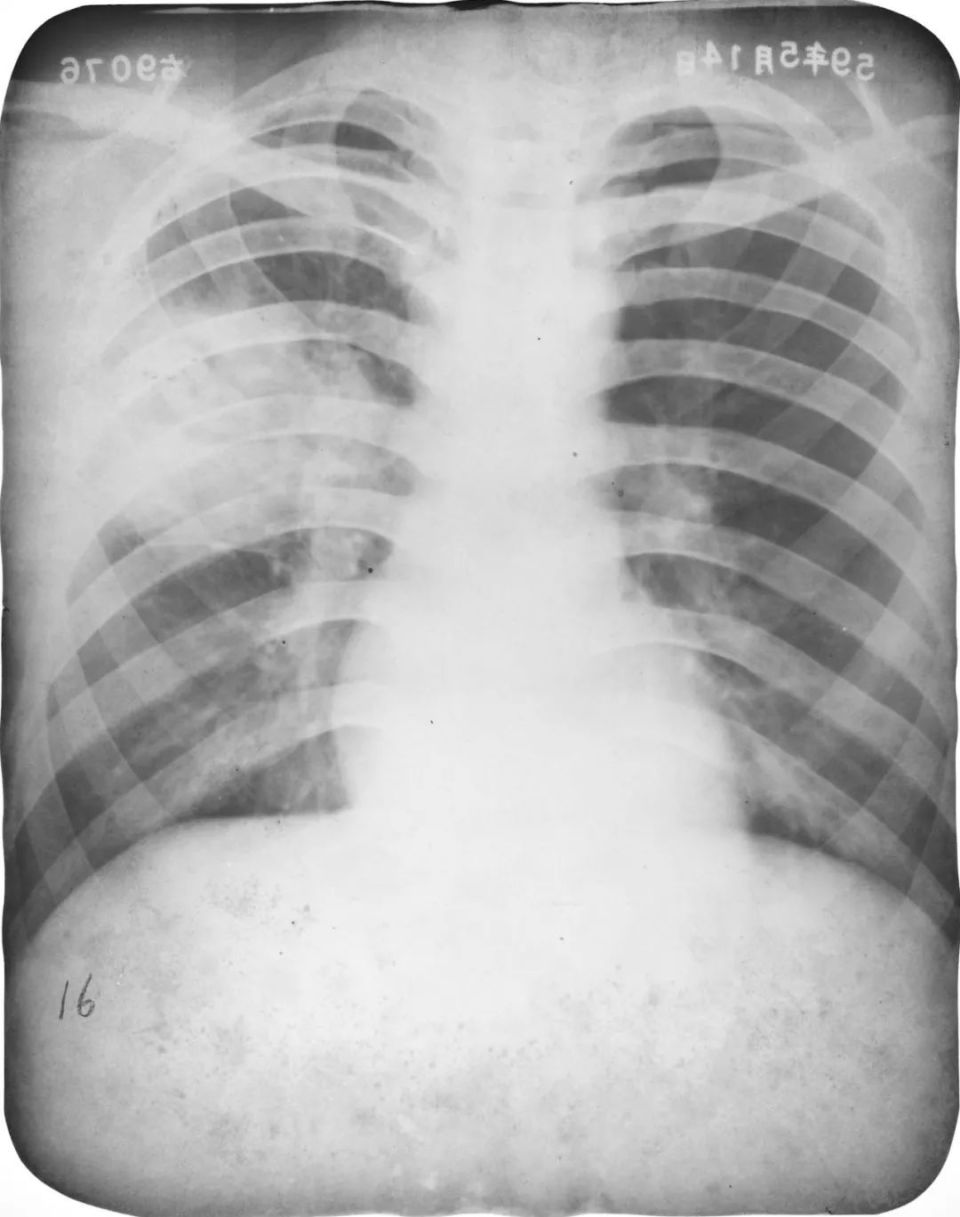

婴幼儿肺炎

图片

胸部正位片示:两肺内带及左肺下野可见不规则的小片状或斑片状边缘模糊的致密阴影,阴影密度不均,局部可见支气管充气征